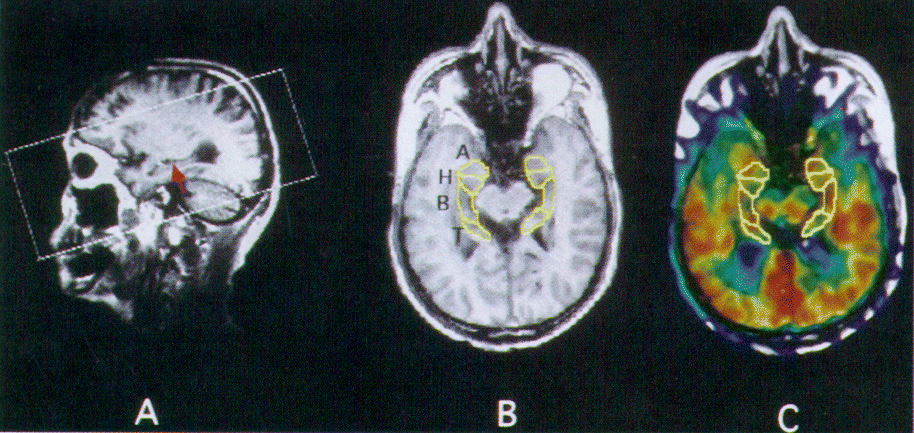

图1所示。(A, B)测定海马纵轴(A)和(B)感兴趣的区域(ROI)设置,检测后菌丝层(箭头)矢状图像,与龙门宠物进行倾斜平行于这个结构,这是一个好标志在决定整个海马结构的纵向方向(见方法)。(C)不规则的roi,双边的细分杏仁核和海马结构在先生的形象,被放置在相应的宠物形象。一个=杏仁核;H =海马头;B =海马的身体;T =海马尾巴。

核磁共振成像过程。MRI是使用一个静态执行磁铁(0.3 T MRP7000AD,日立,东京,日本)收购用以下参数:三维(3 d)模式采样,TR / TE (200 msec / 23 msec), 75度翻转角度,2毫米切片厚度没有差距,和256×256矩阵检测海马结构的纵轴。axis定义线切腹侧边界的菌丝层21(图1一个)。空间关系的中心的中心磁场的宠物已经事先校准图片。这个校准允许我们执行定量PET扫描组平行于任意切割MRI飞机通过倾斜PET探测器环。22执行相同的刚性头固定使用热塑性塑料面罩设计用于外科手术在MRI和PET测量。

不规则感兴趣的区域(roi)大于两个半极大处全宽度(应用)的应用,可以避免部分容积效应的影响,25被画在杏仁核,26海马结构(头、身体、尾巴;看到图1中,B和C),12日,26日和周围的皮质在参考图像先生使用一个图像处理系统(博士看来,透公司,东京,日本)27在SUN工作站上(Hypersparc ss-20, SUN Microsystems,洛杉矶,CA)。重建的宠物,而图像获得海马纵轴平行,理论上不需要重新定位的过程。但是,在某些情况下在扫描头运动,我们不得不重新安排宠物图像在矢状视图博士通过目视检查使用视图成像软件。核磁共振成像立体像素大小调整宠物规整。这些图像,与相同的三维尺度和PET图像坐标,被用作解剖参考以下宠物ROI分析。ROI设置执行主要由两个技术人员不了解病人的诊断。如果完成了ROI设置格式,图片和PET图像显示与图像先生,然后确定ROI是放置在同一地区在先生和相应的宠物图像。因为海马结构约4.5厘米长,1.5 - 2厘米的宽度和深度的头水平,身体水平和1厘米,一个HAP宠物图像压缩数据6.5毫米厚度的海马体的代谢信息包含在z方向。因此,我们认为在HAP的单个图像ROI价值作为地区CMRGlc(体积)的价值。地区CMRGlc平均每个关注区域是由左、右值。